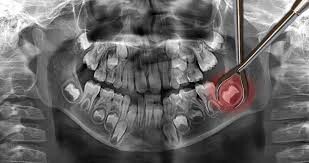

Impacted wisdom teeth hardly ever erupt

Not all wisdom teeth make it out of the gums. Some get impacted, meaning they are trapped in the jawbone or blocked by other teeth. This often happens when the wisdom teeth come in at an awkward angle. Impacted wisdom teeth can cause severe pain and will need to be removed through a surgical procedure.

If you’re a teenager or young adult and your wisdom teeth are growing in, make a dentist appointment to assess whether or not they’ll need to be pulled.

If you let them grow in without this advice, there might not be room in your mouth for all your new teeth. That can lead to an impacted wisdom tooth, which can lead to a really painful infection called pericoronitis.

If your wisdom teeth have already grown in, check them out in the mirror to see if your gums are beginning to grow over them. Sometimes, a gum flap will develop. This is the leading sign of pericoronitis.

If you see these signs and symptoms around your wisdom teeth, make a dentist appointment soon to avoid infection!